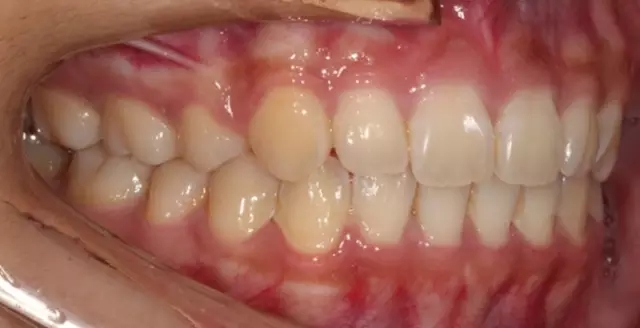

Damon 病例分享:安氏 II 類(lèi)二分類(lèi)露齦笑的矯治(董一磊)

治療前后對(duì)比